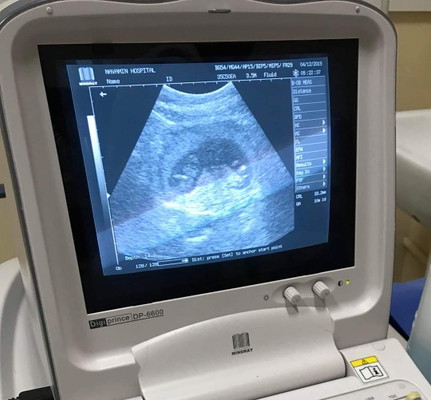

เพิ่งซาวด์เมื่อวานครั้งแรก 11W เป็นเด็กแฝดคะ ดิ้นโชว์ใหญ่เลย อยากเห็นภาพของแต่ละบ้านเด็กแฝดหน่อยคะ